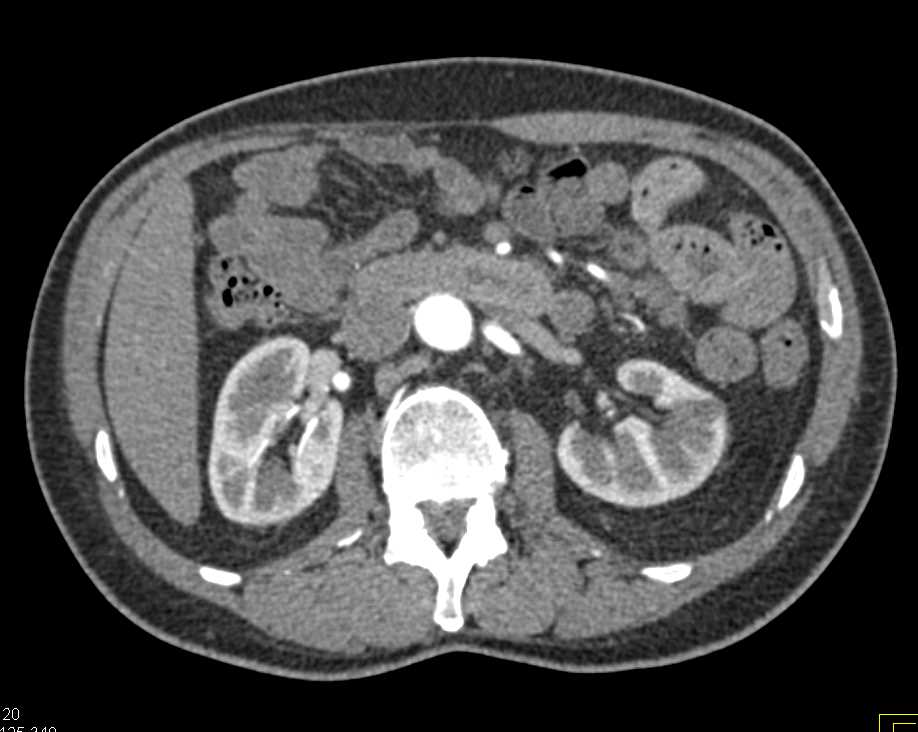

Noncontrast CT scan water density renal mass, compatible with a simple Water Density Renal Cyst But more often, kidney cysts are a type. Kidney cysts are round pouches of fluid that form on or in the kidneys. Kidney cysts can occur with disorders that may impair kidney function. There are two types of kidney cysts: One or more simple cysts may form within the. Kidney cysts (renal cysts) are usually small, round sacs that have. Water Density Renal Cyst.

Benign hyperdense renal cyst. Axial CTscan before (a) and after Water Density Renal Cyst Renal cysts are sacs of fluid that form in the kidneys. Simple cysts and polycystic kidney disease. There are two types of kidney cysts: You might develop one cyst or. As you get older, cysts can form on the. One or more simple cysts may form within the. Simple cysts are individual cysts that form on. Kidney cysts are round. Water Density Renal Cyst.